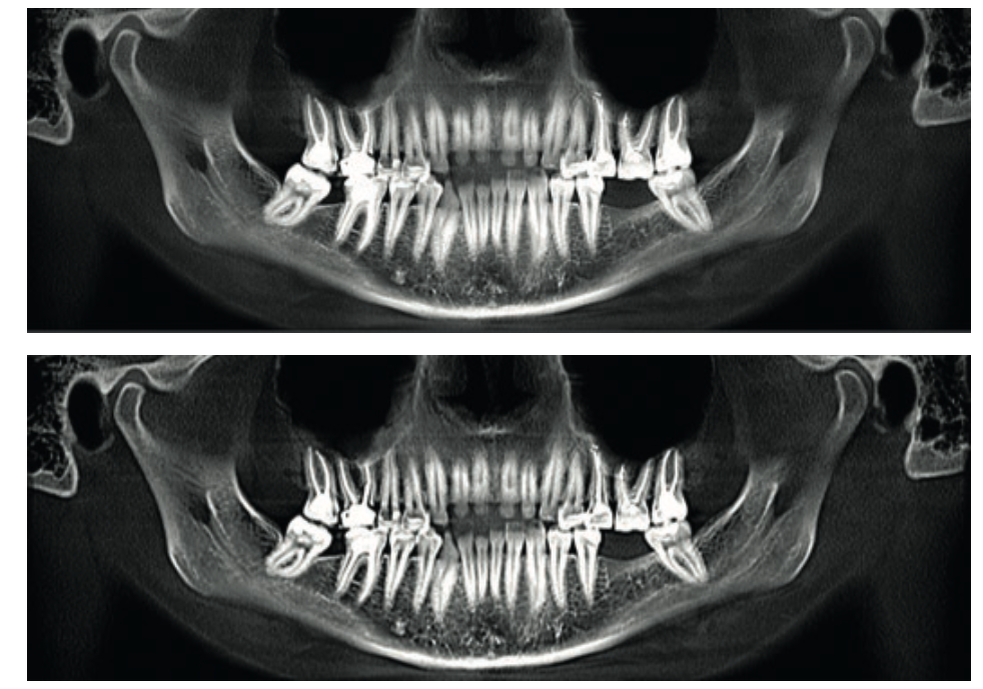

Методическое пособие, А. Потапов, стр. 11 и стр. 13